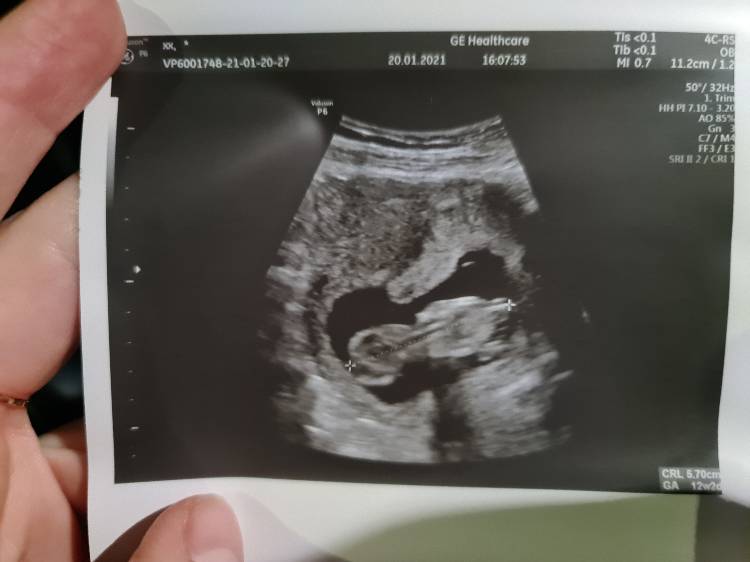

Fanka BB :)